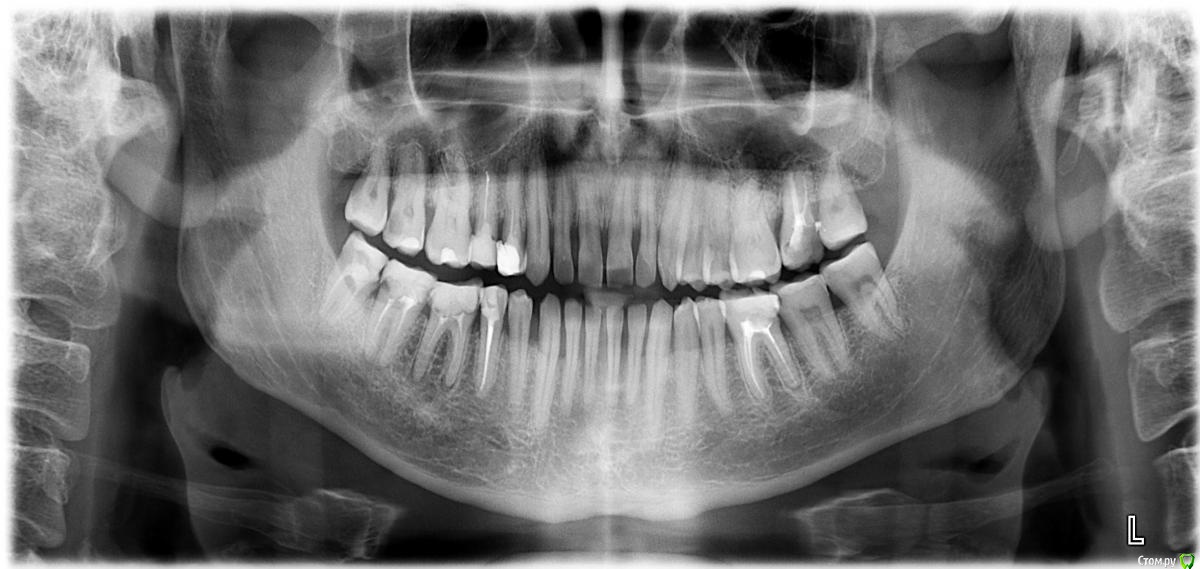

andrei-gpn Опубликовано 11 марта, 2015 Поделиться Опубликовано 11 марта, 2015 Добрый день! Проконсультируйте пожалуйста.Мне 32 года, около месяца назад, очень сильно воспалились десна на нижней челюсти, в районе центральных зубов, чуть позже встали воспаляться десна и наверху. Воспаление длилось около недели, потом начало спадать. На приеме у пародонтолога проведена профессиональная чистка и поставлен диагноз генерализованный пародононтит тяжелой степени, и подвижность отдельных 1 степени ( нижние центральные зубы имеют небольшую подвижность), плюс образовалось несколько карманов, ну а про кровоточивость десен я уже не говорю, после того как бросил курить, это стало постоянным явлением. рекомендовано оперативное лечение обоих челюстей ( видимо имелся ввиду открытый кюретаж). Так вот, действительно ли я нуждаюсь в оперативном лечении, будет ли эффект от этой операции ( пародонтолог предупредил, что после операции десна опустится), есть ли возможность как то исправить ситуацию, может в моем случае будет достаточно вектора. Большое спасибо, снимок прилагаю. Ссылка на комментарий

red_butler Опубликовано 11 марта, 2015 Поделиться Опубликовано 11 марта, 2015 Для начала санация и вектор или закрытый кюретаж. Для полноценного ответа нужен очный осмотр, если судить только по снимку - пародонтит средней степени Ссылка на комментарий

Гарриевич Опубликовано 11 марта, 2015 Поделиться Опубликовано 11 марта, 2015 Вам нужны убрать из полости рта все старые пломбы с нависающими краямиперелечить 15, 14, 27,36, 46, 47 зубы и покрыть их коронкамипролечить 17 и тоже подумать о коронкеи решить с 48 вопрос Ссылка на комментарий